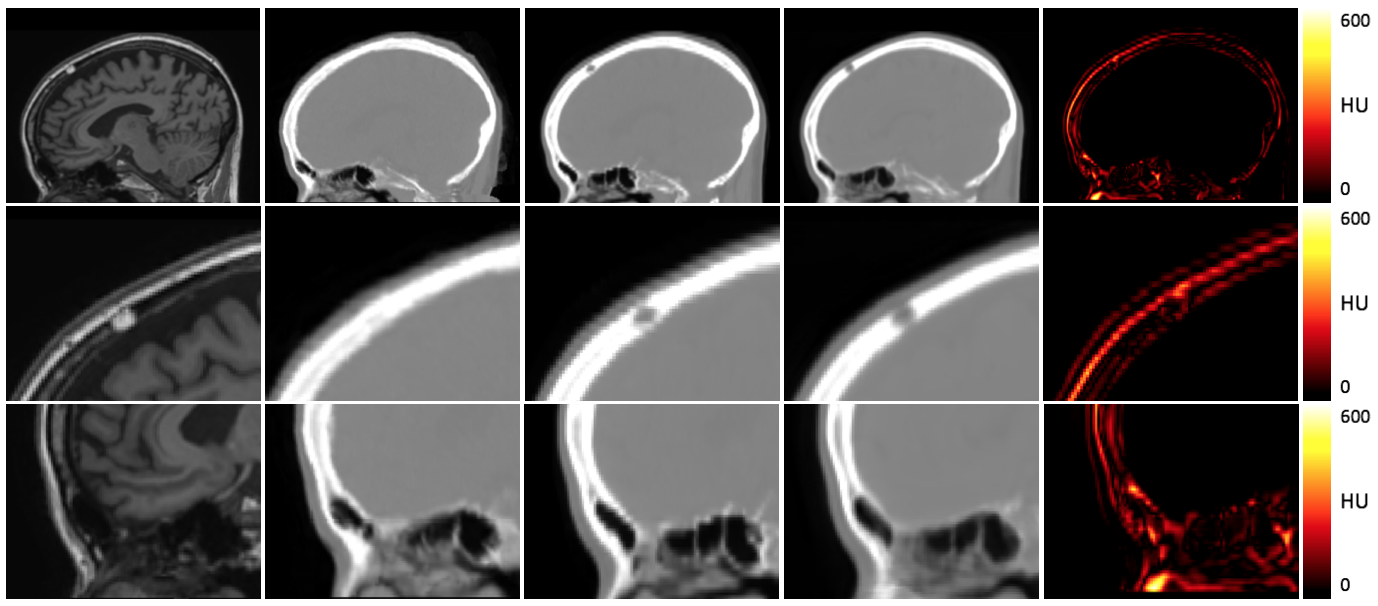

Figure 3 shows an example MR input image, a synthesised CT image obtained by a current state-of-the-art multi-atlas propagation approach [1], a synthesised CT generated by the proposed deep boosting approach and the corresponding reference CT images. Other than the multi-atlas propagation method, our network is able to generate details in the pseudo CT that the network has never seen. For example, Fig. 3 shows a patient with an epidermoid cyst in the skull being correctly generated by the network, even though no other patient in the training database shows a similar anatomical abnormality. The greatest error can be observed at the contour of the head and air, especially in the region of the nasal cavity.

Refer to caption

Figure 3: From left to right: Input MR image, synthesised CT using multi-atlas propagation approach, reference real CT, synthesised CT using proposed Deep Boosted Regression, and absolute error between real and synthesised boosted CT images of the whole head (top), an anatomical abnormality in the skull (middle) and the sinus region (bottom).